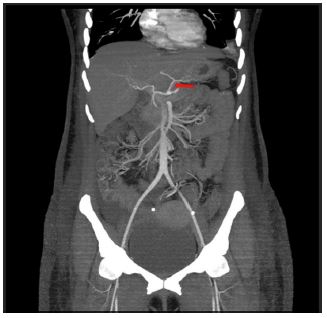

Figure 5: Coronal CT reformats showing the origin of LHA (red arrow) arising from LGA.

Figure 6: Coronal CT reformats showing the origin of RHA (red arrow) arising from SMA.

The latter two variants have often been described as “double hepatic arteries” [1].

The newly found hepatic artery variant (not described in the standard classification) was an accessory LHA (origin of LHA from LGA) along with the presence of an accessory right hepatic artery (origin of RHA from SMA) (Figures 5 and 6). This was seen in 3.5% of the total population.